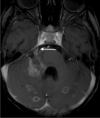

Tuberculosis (TB) remains one of the major public health threats worldwide, despite improved diagnostic and therapeutic methods. Tuberculosis is one of the main causes of infectious disease in the chest and is associated with substantial morbidity and mortality in paediatric populations, particularly in low- and middle-income countries. Due to the difficulty in obtaining microbiological confirmation of pulmonary TB in children, diagnosis often relies on a combination of clinical and radiological findings. The early diagnosis of central nervous system TB is challenging with presumptive diagnosis heavily reliant on imaging. Brain infection can present as a diffuse exudative basal leptomeningitis or as localised disease (tuberculoma, abscess, cerebritis). Spinal TB may present as radiculomyelitis, spinal tuberculoma or abscess or epidural phlegmon. Musculoskeletal manifestation accounts for 10% of extrapulmonary presentations but is easily overlooked with its insidious clinical course and non-specific imaging findings. Common musculoskeletal manifestations of TB include spondylitis, arthritis and osteomyelitis, while tenosynovitis and bursitis are less common. Abdominal TB presents with a triad of pain, fever and weight loss. Abdominal TB may occur in various forms, as tuberculous lymphadenopathy or peritoneal, gastrointestinal or visceral TB. Chest radiographs should be performed, as approximately 15% to 25% of children with abdominal TB have concomitant pulmonary infection. Urogenital TB is rare in children. This article will review the classic radiological findings in childhood TB in each of the major systems in order of clinical prevalence, namely chest, central nervous system, spine, musculoskeletal, abdomen and genitourinary system.